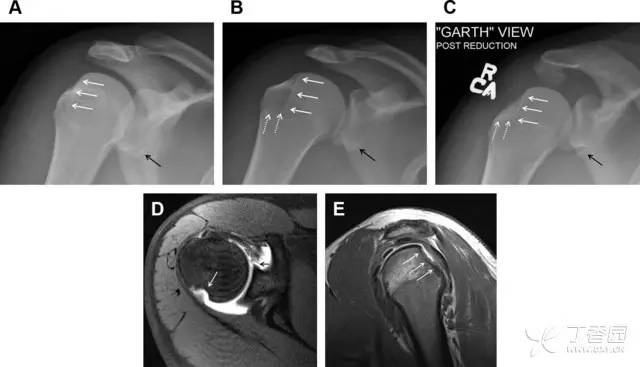

膝关节撕脱骨折和压缩骨折常伴发于韧带损伤,若想准确诊断,在了解这些骨折高发部位的同时,还需仔细认真地阅片,否则有些骨折就被漏诊了。

前交叉韧带撕脱骨折常发生在胫骨髁间嵴(图 1)。这种骨折在青少年中常见,但在成年人中也并不像大家想象的那么少见。

图 1 摩托车事故患者前交叉韧带撕脱性骨折

A 正位片示胫骨髁间嵴底部骨折(箭头),注意别把这个骨折碎片错认为关节内结构。B 侧位片示胫骨上方可见一细长型骨折碎片(椭圆)。C MRI 矢状位 T2 加权像示前交叉韧带附着于撕脱的骨折碎片上(箭头),注意周围存在骨髓水肿和积脂血征(空箭头)。

图 2 扭伤后的股骨外侧髁凹陷征

A 侧位片示股骨外侧髁凹陷。B MRI 矢状位 T2 加权像示股骨外侧髁及胫骨后外侧骨挫伤(空箭头)。胫骨近端随着后交叉韧带撕裂发生移位,露出外侧半月板的后角(弧形箭头)。

胫骨后外侧小片骨皮质的压缩性骨折,可能是旋转移位损伤的唯一证据(图 3)。这种骨折在常规膝关节平片很难发现,若怀疑存在骨折,行下肢内旋斜位片检查可诊断。

图 3 胫骨后外侧碎片骨折

A 正位片示胫骨后外侧处可见一压缩骨折的小碎片(方框)。这是胫骨撞击股骨外侧髁旋转移位时所致。B 另一位患者的 MRI 矢状位 T1 加权像示胫骨后外侧骨折碎片(箭头)。

Segond 骨折是发生在胫骨平台外侧的垂直撕脱性骨折(图 4)。这种骨折在前后位 X 线片上显示最佳。

屈曲位时膝关节受到内旋*力暴**作用,导致皮质骨撕脱性骨折,这种骨折常发生在运动员身上。常引起股骨内髁和胫骨平台后内侧骨挫伤,75%~100% 的患者伴前交叉韧带断裂,33% 的患者伴外侧半月板损伤。

图 4 一位足球运动员的 Segond 骨折

A 正位片示关节线下方胫骨外侧皮质撕脱(箭头)。B MRI 冠状位 T1 加权像示附着于髂胫带的骨折碎片(空箭头)。